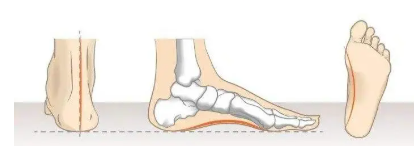

Zhengzhou Zhenshan Medical Equipment Co., Ltd. was formally established in 2017. The company specializes in R&D, production and sales of rehabilitation aids and consumables, including orthoses, low-temperature thermoplastic sheets and orthopedic insoles. The company has a strong R&D team, a professional marketing team and a perfect after-sales service system. The products are mainly exported to Europe, Southeast Asia, the Middle East, Africa and many other countries."People-oriented, scientific spirit, win-win cooperation, continuous learning" is our company's corporate values. We will do our best to serve every customer, produce better products, and make due contributions to the medical device industry! We look forward to cooperating with you to create a brilliant future!